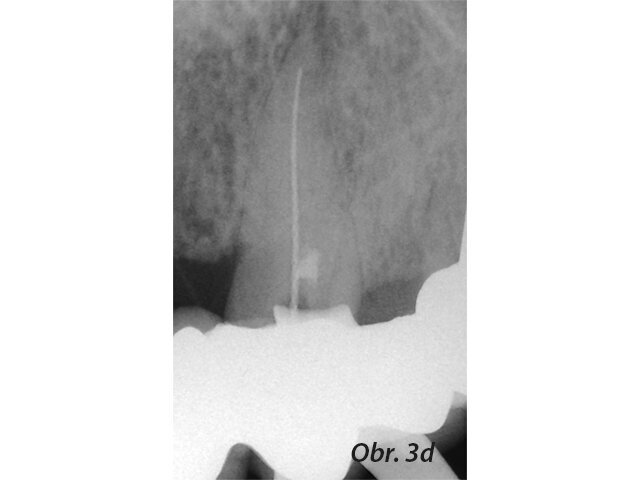

Kořenové perforace

Perforace v dřeňové dutině nebo kořenovém kanálku významně mění prognózu zubu. Oprava perforace pomocí biokompatibilního těsnicího materiálu jako je MTA může ohrožené zuby ušetřit (Mente a spol. 2014) (obr. 3a–e).

Původní stav se zaplněnou perforací

Postoperační RTG se zaplněným kanálkem